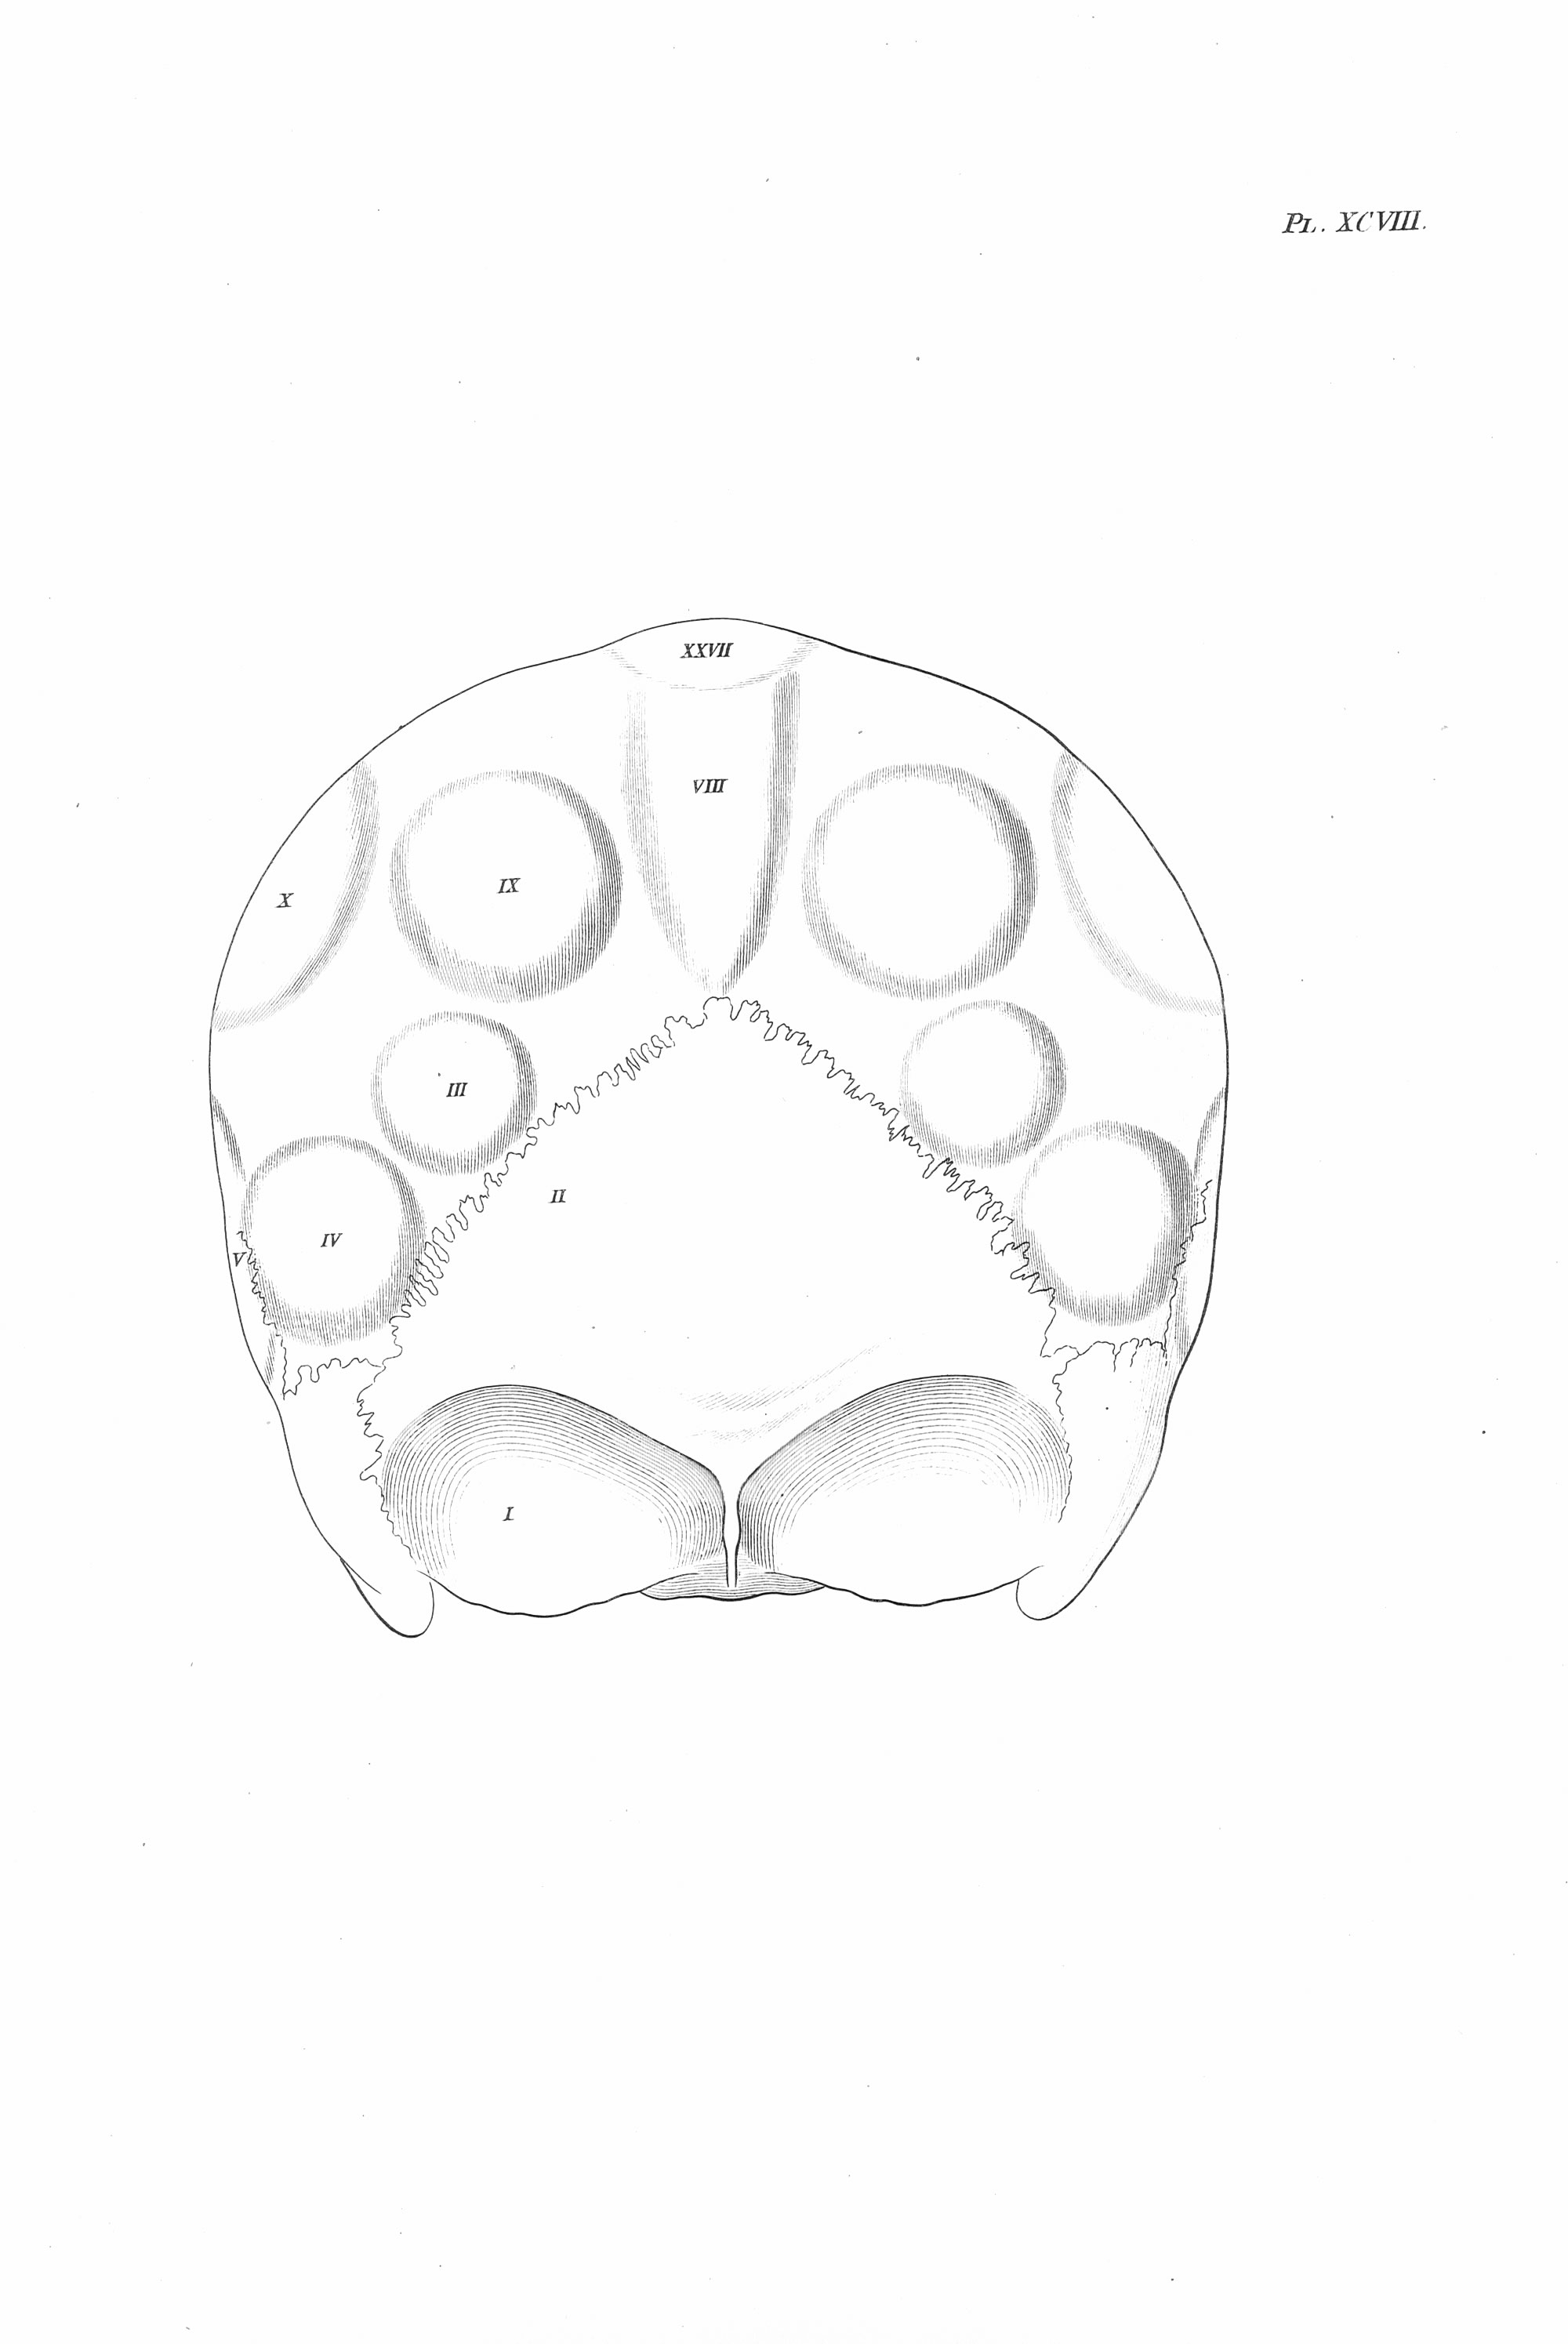

Gall: Plates

Gall, F. J. (1818). Anatomie et physiologie du système nerveux en général, et du cerveau en particulier, Avec des observations sur la possibilité de reconnoître plusieurs dispositions intellectuelles et morales de l´homme et des animaux, par la configuration de leurs têtes.

Librairie Grecque-Latine-Allemande, Vol. 3, I-XXXV u. 1-379 100 planches.